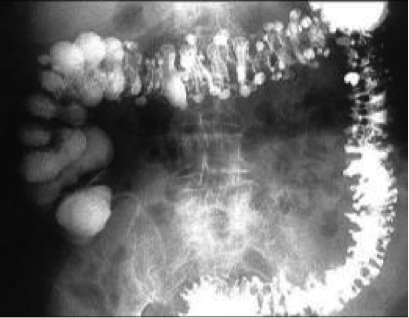

Describe the appearance of residual contrast material in diverticulum.

“Chocolate-chip sign”; dots across the whole pelvis